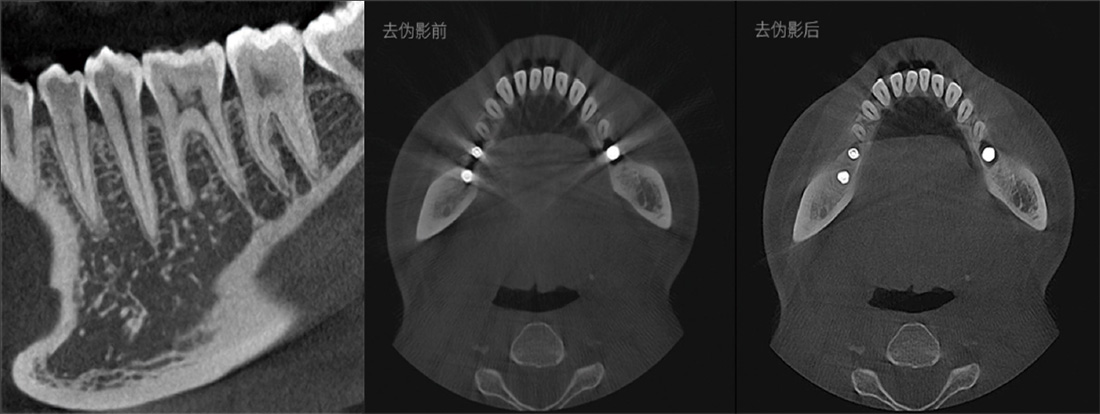

El modo de alta definición, HD75µm, puede afrontar diagnósticos de conductos radiculares difíciles.

Representación del tubo neural

- Comprobar la dirección del tubo neural y su relación con la posición de las muelas del juicio

- Comprobar la distancia entre el tubo neural y el implante para evitar que el implante toque el tubo neural